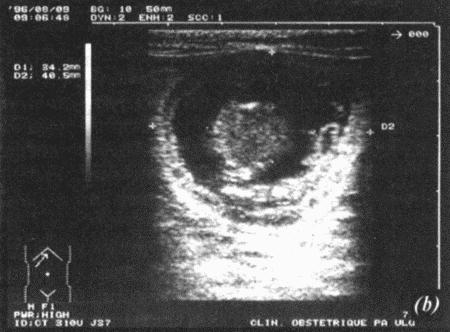

Фиг. 17.2.

Ультрасонографическое изображение (а, b) нормальная беременность (38 дней) в результате естественной вязки; (с) резорбция эмбрионов, индуцированная каберголином в сочетании с простагландином